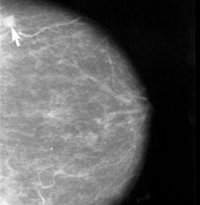

Especialistas del Hospital Universitari i Politècnic La Fe de València han participado en el estudio OlympiAD, un ensayo internacional sobre la efectividad de un fármaco en la reducción de recaída o muerte en pacientes de cáncer de mama, según ha indicado la Generalitat en un comunicado.

Los últimos resultados positivos del ensayo Fase III OlympiAD se han presentado en el Congreso Anual de la Sociedad Americana de Oncología Clínica, celebrado en Chicago (Estados Unidos. Estos datos muestran la mejora clínica y estadísticamente significativa en la supervivencia libre de progresión de las pacientes con cáncer de mama metastásico HER2 negativo con mutaciones en los genes BRCA 1 /2 en línea germinal, tratadas con olaparib, frente al tratamiento estándar con quimioterapia.

Concretamente, el ensayo mostró que en pacientes tratadas con olaparib se redujo hasta un 42 por ciento el riesgo de empeoramiento de la enfermedad o muerte, frente a aquellas que recibieron quimioterapia. Estos resultados se han publicado en la revista The New England Journal of Medicine.